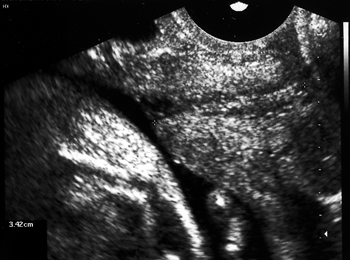

Εικόνα 2. Βραχύς τράχηλος με funneling (διακολπικό υπερηχογράφημα).